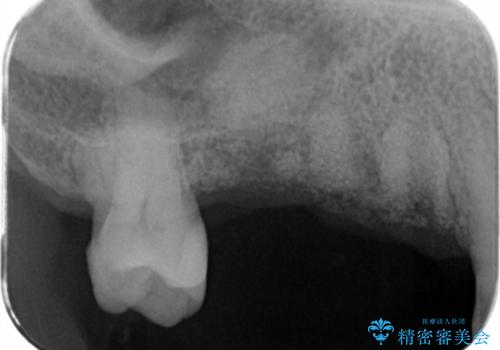

- 右上の奥歯を失ってしまい、「全然モノが噛めない、しっかりと噛めるようになりたい。」

、と入れ歯ではなくインプラント治療を希望され来院されました。

3本の歯が失われた状態を、2本のインプラントで支えるブリッジでの咬合機能回復を計画します。